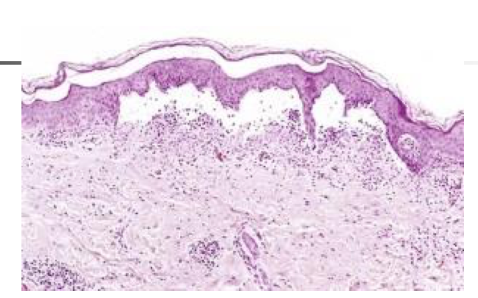

describe what is seen in the image

Q